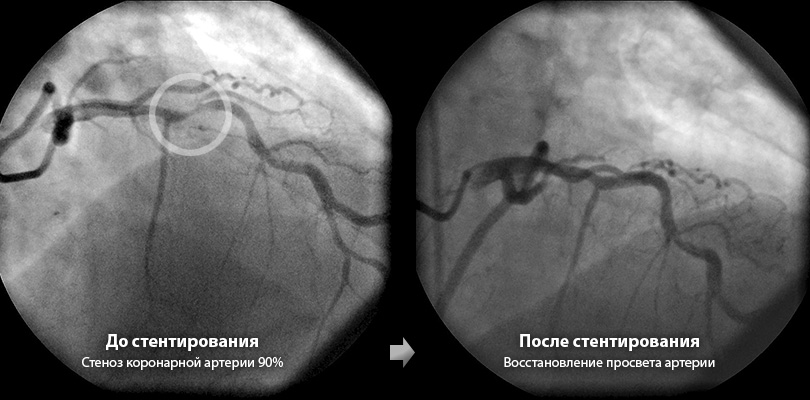

Чтобы преодолеть эти недостатки ангиопластики, были разработаны стенты. Это устройство представляет собой тонкую трубку из ячеистого металла. Его вводят в суженный участок сосуда с помощью баллонного катетера. После введения стент расправляется, расширяя просвет артерии, что позволяет крови свободно течь через него. Стентирование значительно улучшает качество жизни пациентов с ишемией, снижает риск осложнений, облегчает боль при стенокардии и предотвращает сердечные приступы.